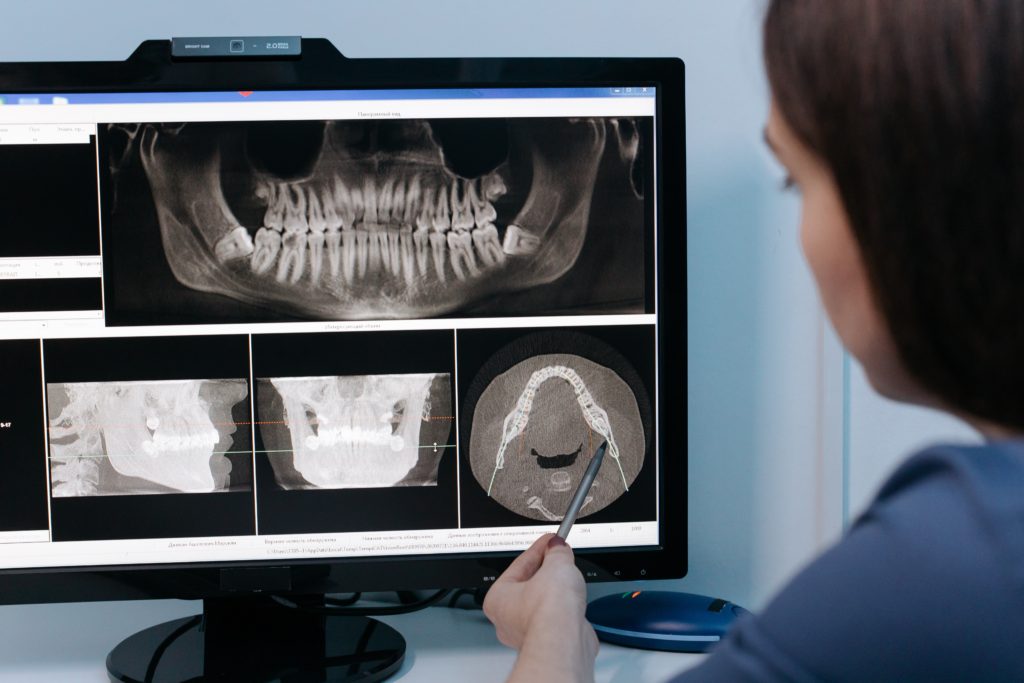

X-Ray Certification for Dental Assistants is essential. This course prepares students for employment as a Dental Assistant by training them in both X-Ray Preparation and X-Ray Exposure, later allowing them to gain their certification. Our X-Ray Certification for dental assistants course includes education about radiation safety, production of x-rays, and oral radiography (digital and traditional), along with learning how to operate dental x-ray equipment under the supervision of a certified dentist.